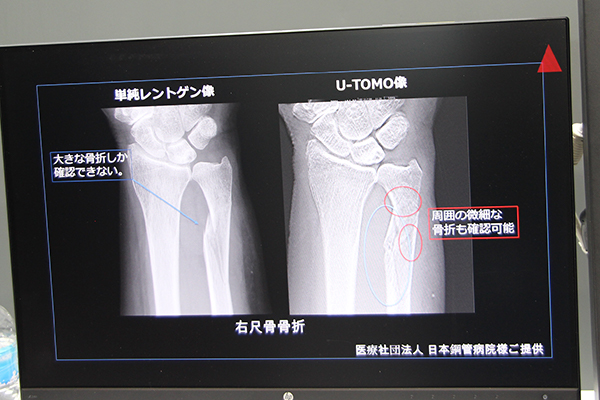

さらに,既存の一般X線撮影装置でトモシンセシス撮影を可能にする“ユニバーサルトモシンセシス”(W.I.P.)を紹介した。これは,専用ファントムとともに患部を角度を変えて複数回撮影し,ファントム像からエックス線撮影装置のアライメントを算出,得られた画像を断層画像として再構成するもの。H/W(PC)とソフトウエアを追加するだけで,既存の一般X線撮影装置で撮影,再構成が可能な点が利点である。四肢や股関節などが対象で,撮影には1〜2分を要することから,固定具も開発中である。通常の検査では,微細な骨折などは見逃されることも多く,疼痛の長期化や他疾患の誘発につながる懸念が大きい。しかし,このようなアプリケーションの活用により,早期発見が可能になれば,健康寿命の延伸に貢献しうる。また,コニカミノルタ社と開発した動態イメージングも紹介した。これは,一般X線撮影装置で撮影した画像を動画にすることができ,慢性閉塞性肺疾患(COPD)などの呼吸器疾患の早期発見が期待される。

“ユニバーサルトモシンセシス”の概要(W.I.P.)

“ユニバーサルトモシンセシス”(W.I.P.)で取得した画像(右)。周囲の微細な骨折も確認できる。